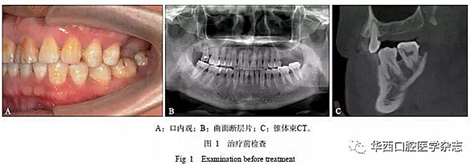

患者男性,45歲,2015年10月由四川大學(xué)華西口腔醫(yī)院種植科轉(zhuǎn)診,主訴“左上后牙缺失,種植前要求壓低左下后牙”。口內(nèi)檢查見上下牙列無擁擠,25與35牙為中性關(guān)系,26、27牙缺失,36、37牙伸長(zhǎng)(圖1A)。

1)正畸治療前完善影像學(xué)檢查(圖1B、C)及牙周基礎(chǔ)治療;